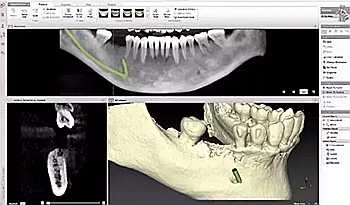

5、不愿意拍牙片

一些人不愿意照牙片,認(rèn)為醫(yī)生看看牙齒情況就可以了。

要知道醫(yī)生的眼睛不是透視鏡,牙齒好比大樹,樹根扎在土壤里,而我們的牙根也埋在牙槽骨里,牙根的狀態(tài)、里面的神經(jīng)肉眼都是看不到的。

只有通過牙片,牙醫(yī)才可以確切了解齲壞的范圍、牙痛是由牙髓炎還是根尖炎或是牙周炎引起、種植牙需要的骨量等等。

牙疼才去看牙?牙科最良心科普都在這里了!

圖:種植牙牙片

牙片為醫(yī)患溝通提供了準(zhǔn)確的依據(jù)。

有些家長(zhǎng)還認(rèn)為孩子拍牙片會(huì)受到輻射,對(duì)身體不好,其實(shí)大可不必?fù)?dān)心,牙科X光片對(duì)身體輻射量相當(dāng)?shù)停⑶艺?guī)牙科都會(huì)配備防輻射服,影響微不足道。

建議

相信醫(yī)生,拍牙片只能對(duì)你有好處,也可以為你保留最原始資料,更可以讓醫(yī)生準(zhǔn)確判斷你的病情,更好地為你治療。